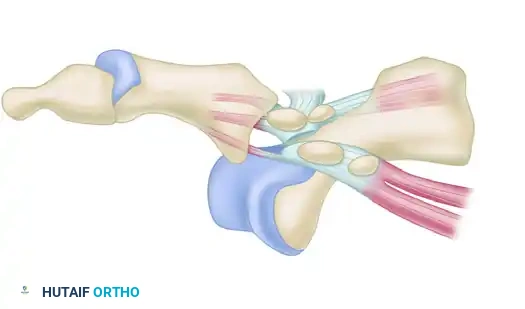

Type IIB Dislocation

A Type IIB dislocation involves a transverse fracture of one of the sesamoids (usually the medial sesamoid) along with a rupture of the intersesamoid ligament.

FIGURE 88-78 D: Type IIB dislocation. The sesamoid fracture acts as a release, often permitting closed reduction, though surgical repair may be indicated for the fracture.

Step 3: The Reduction Maneuver

- Do not simply pull longitudinally on the toe, as this will tighten the intrinsic muscles around the metatarsal neck.

- Instead, insert a small Freer elevator or a smooth periosteal elevator into the joint space.

- Hyperextend the great toe to recreate the deformity and relax the plantar structures.

- While maintaining hyperextension, apply gentle distal traction.

- Use the Freer elevator to carefully pry and guide the base of the proximal phalanx over the dorsal lip of the metatarsal head.

- Once the phalanx clears the metatarsal head, plantarflex the toe to snap the joint into its anatomically reduced position.